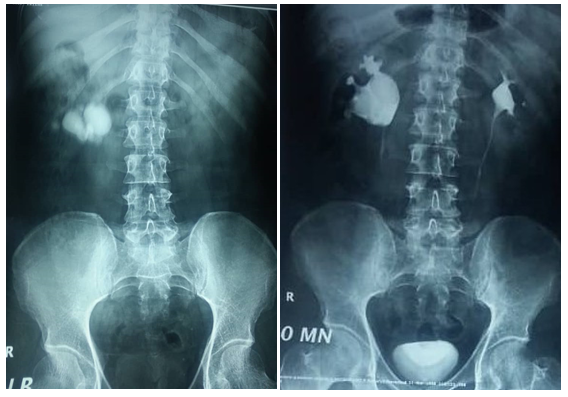

45 years old male patient came to urology outpatient complaining of recurrent right flank pain for several months, no fever or hematuria, no significant medical or surgical history. Physical examination was unremarkable, serum creatinin 1.1mg/dl , urine analysis showed microscopic hematuria, urine culture was negative, ultrasound reveals multiple right renal stones with dilated extrarenal pelvis, plain x ray & intravenous pyelography performed Figure1 (A & B). All treatment options explained to the patient and after discussion he elected to undergo laparoscopic peylolithotomy. Transperitoneal laparoscopic pyelolithotomy was performed in lateral position with Rt. Flank tilted 45 degrees using 4 ports. multiple renal pelvis and calyceal stones extracted and putted in a bag made of No 6 surgical glove (Figure 2) after closure of the pyelotomy by intracorporeal sutures the bag containing the stones extracted through the umbilical port after enlarging it (Figure 2), during extraction the bag was broken and some stones escaped to the abdomen. Another bag replaced and most of the stones extracted searching for the remaining stones in the abdomen was frustrating and we decided to terminate the procedure and closing the port sites. The post-operative course is unremarkable and patient discharged in fifth post-operative day. Follow up plain x-ray after one month revealed tow round stones with 30 and 10mm maximum diameter lying deep in the pelvis (Figure 3), after discussion with the patient about the possible complications of those stones he agree to underwent open extraction by low midline incision and stones extracted.

Figure 3 Post operative x ray showing lost stones in the pelvis.